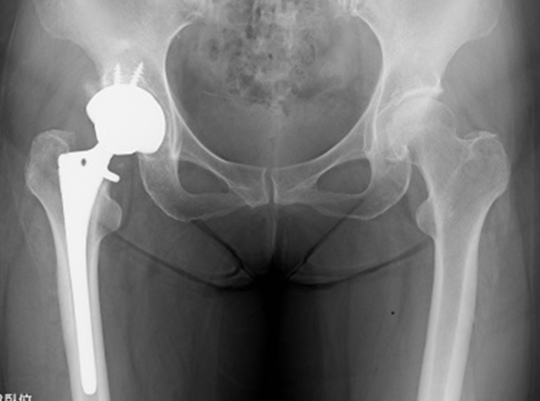

繰り返される股関節痛の最終形態がOPE

でなけらば、60代または70代で手術する可能性があるからです。

ヒトのカラダは1回 悪くなったものを変える方法は手術しかありません。

いかに「手術しない! させない!」ためには、腰椎・骨盤・股関節の機能を修正すること!